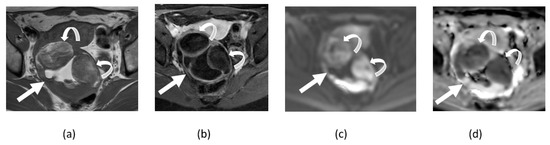

3.2. Adnexal Torsion

3.3. Endometriosis

3.4. Tubo-Ovarian Abscess

3.5. Mature Cystic Teratoma

3.6. Ovarian Fibroma, Fibrothecoma, and Thecoma